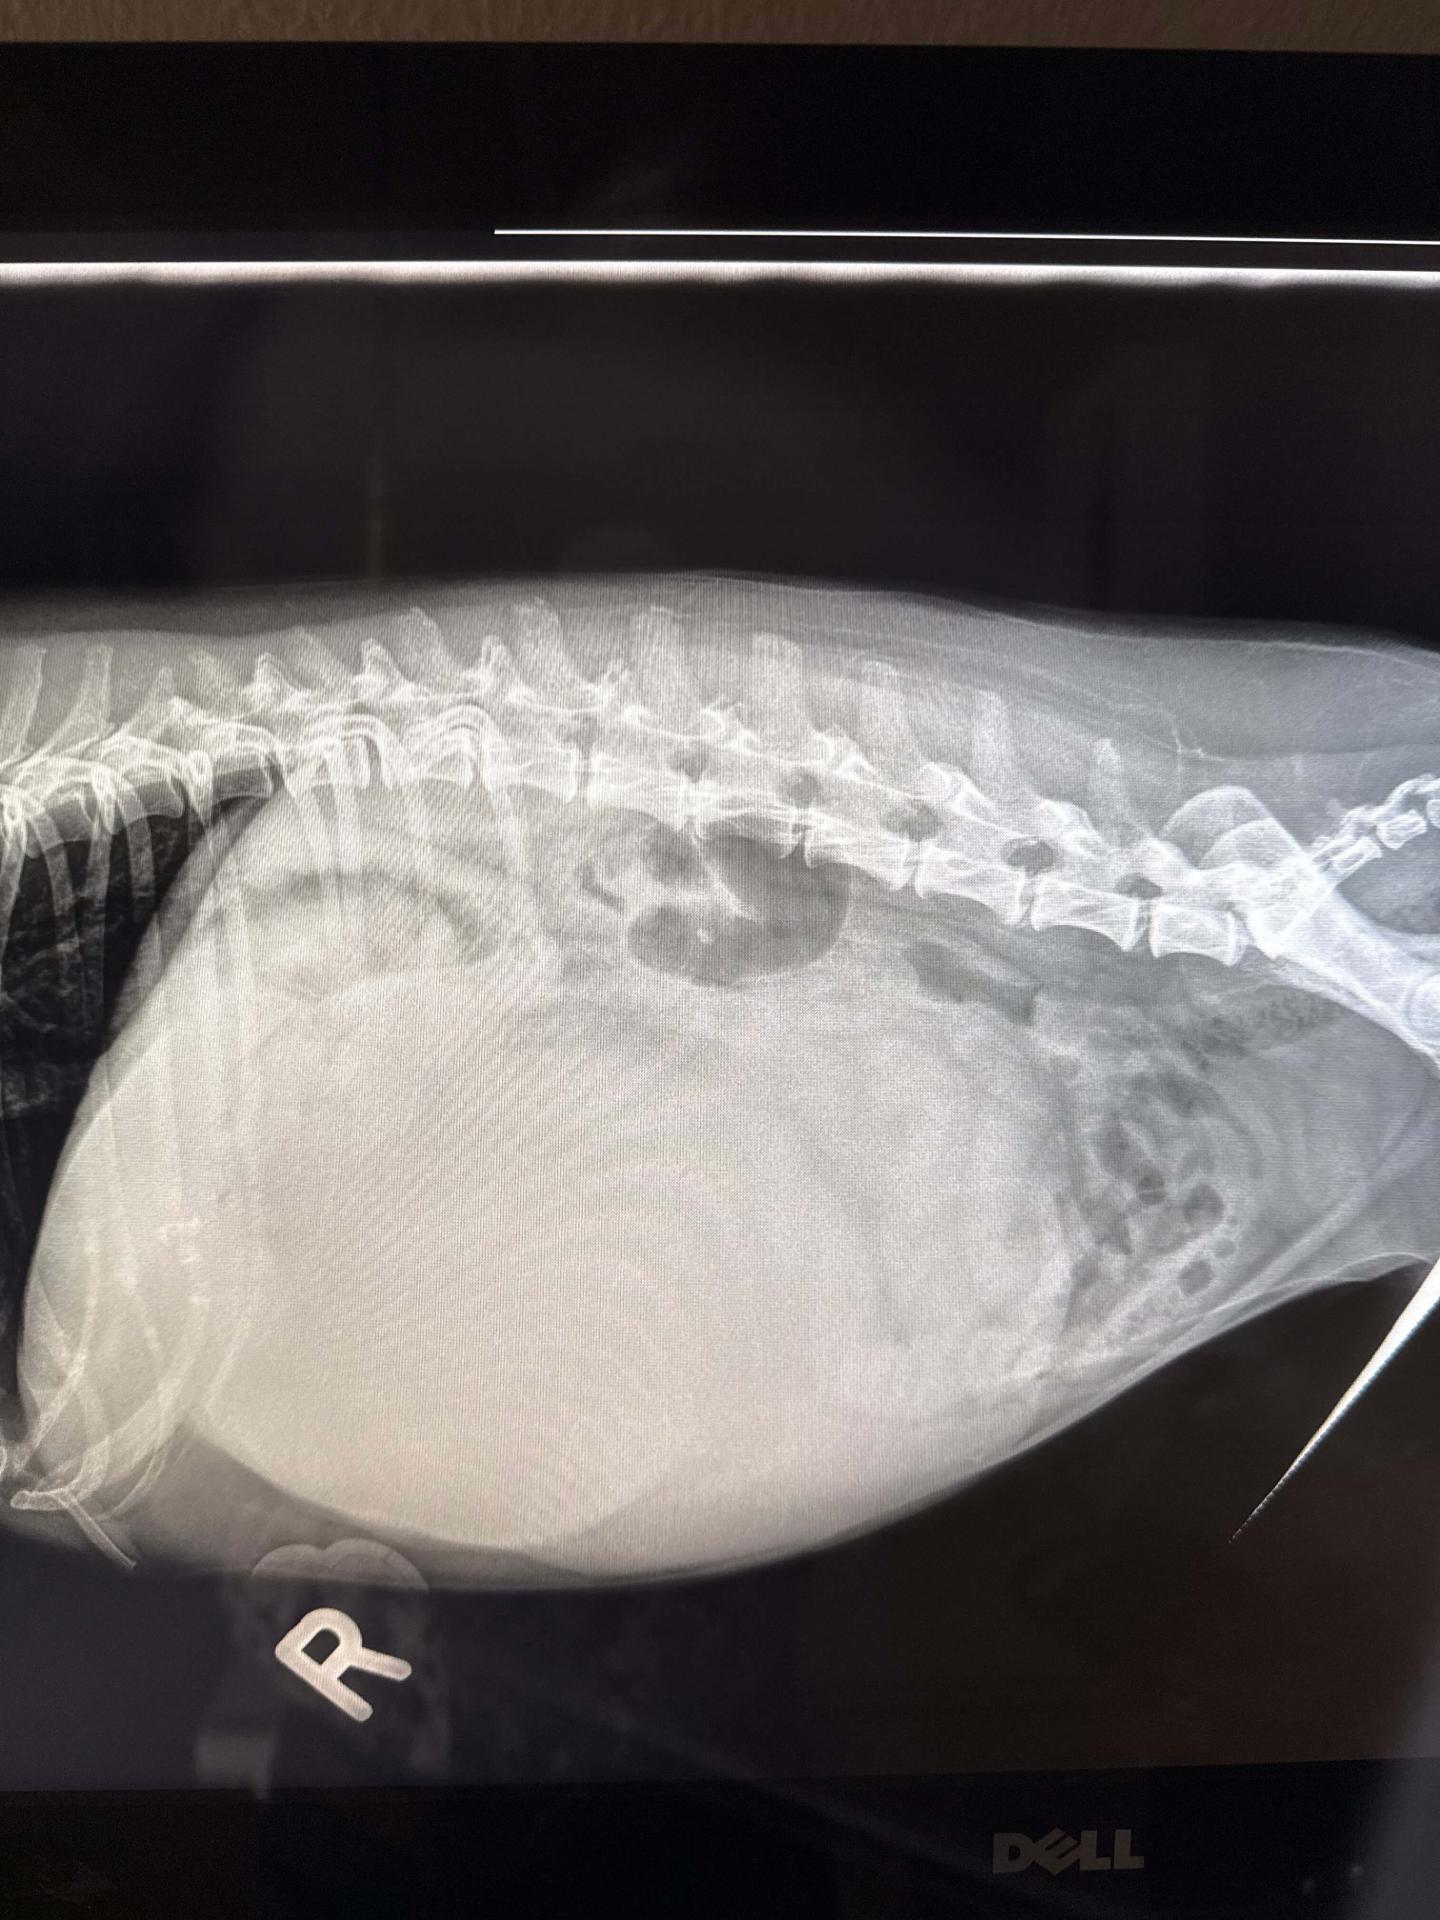

A 9 year old female spayed maltese presented for lack of appetite, weight loss and tremendously enlarged belly. She was also lethargic with reluctance to walk or jump.

Her examination showed a firm, pendulous abdomen with extreme muscle and fat loss over the remainder of her body. She was extremely weak and lethargic.

Imaging and labwork were performed to determine the source of the symptoms. A baseball-sized mass was identified in the abdomen, attached to either the liver or spleen.